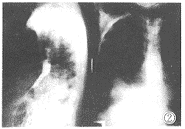

讨论肺硬化性血管瘤(PSH),多见于女性,男性少见,其X 线表现主要以肺内孤立性块影或结节影为主。亦有报道表现为 广泛的粟粒样微小结节。本病例表现为肺内巨大肿块向纵隔 延伸,边缘不光滑,密度不均匀。其内有部分沙砾样高密度阴 影,并压迫食道引起食道不完全性梗阻(图1,2)。

图1 右肺下叶及右中后、中下纵隔肿瘤并部分沙砾样致密影。

图2 膈上段食道充盈缺损,钡剂通过困难,梗阻部上端食道扩张。